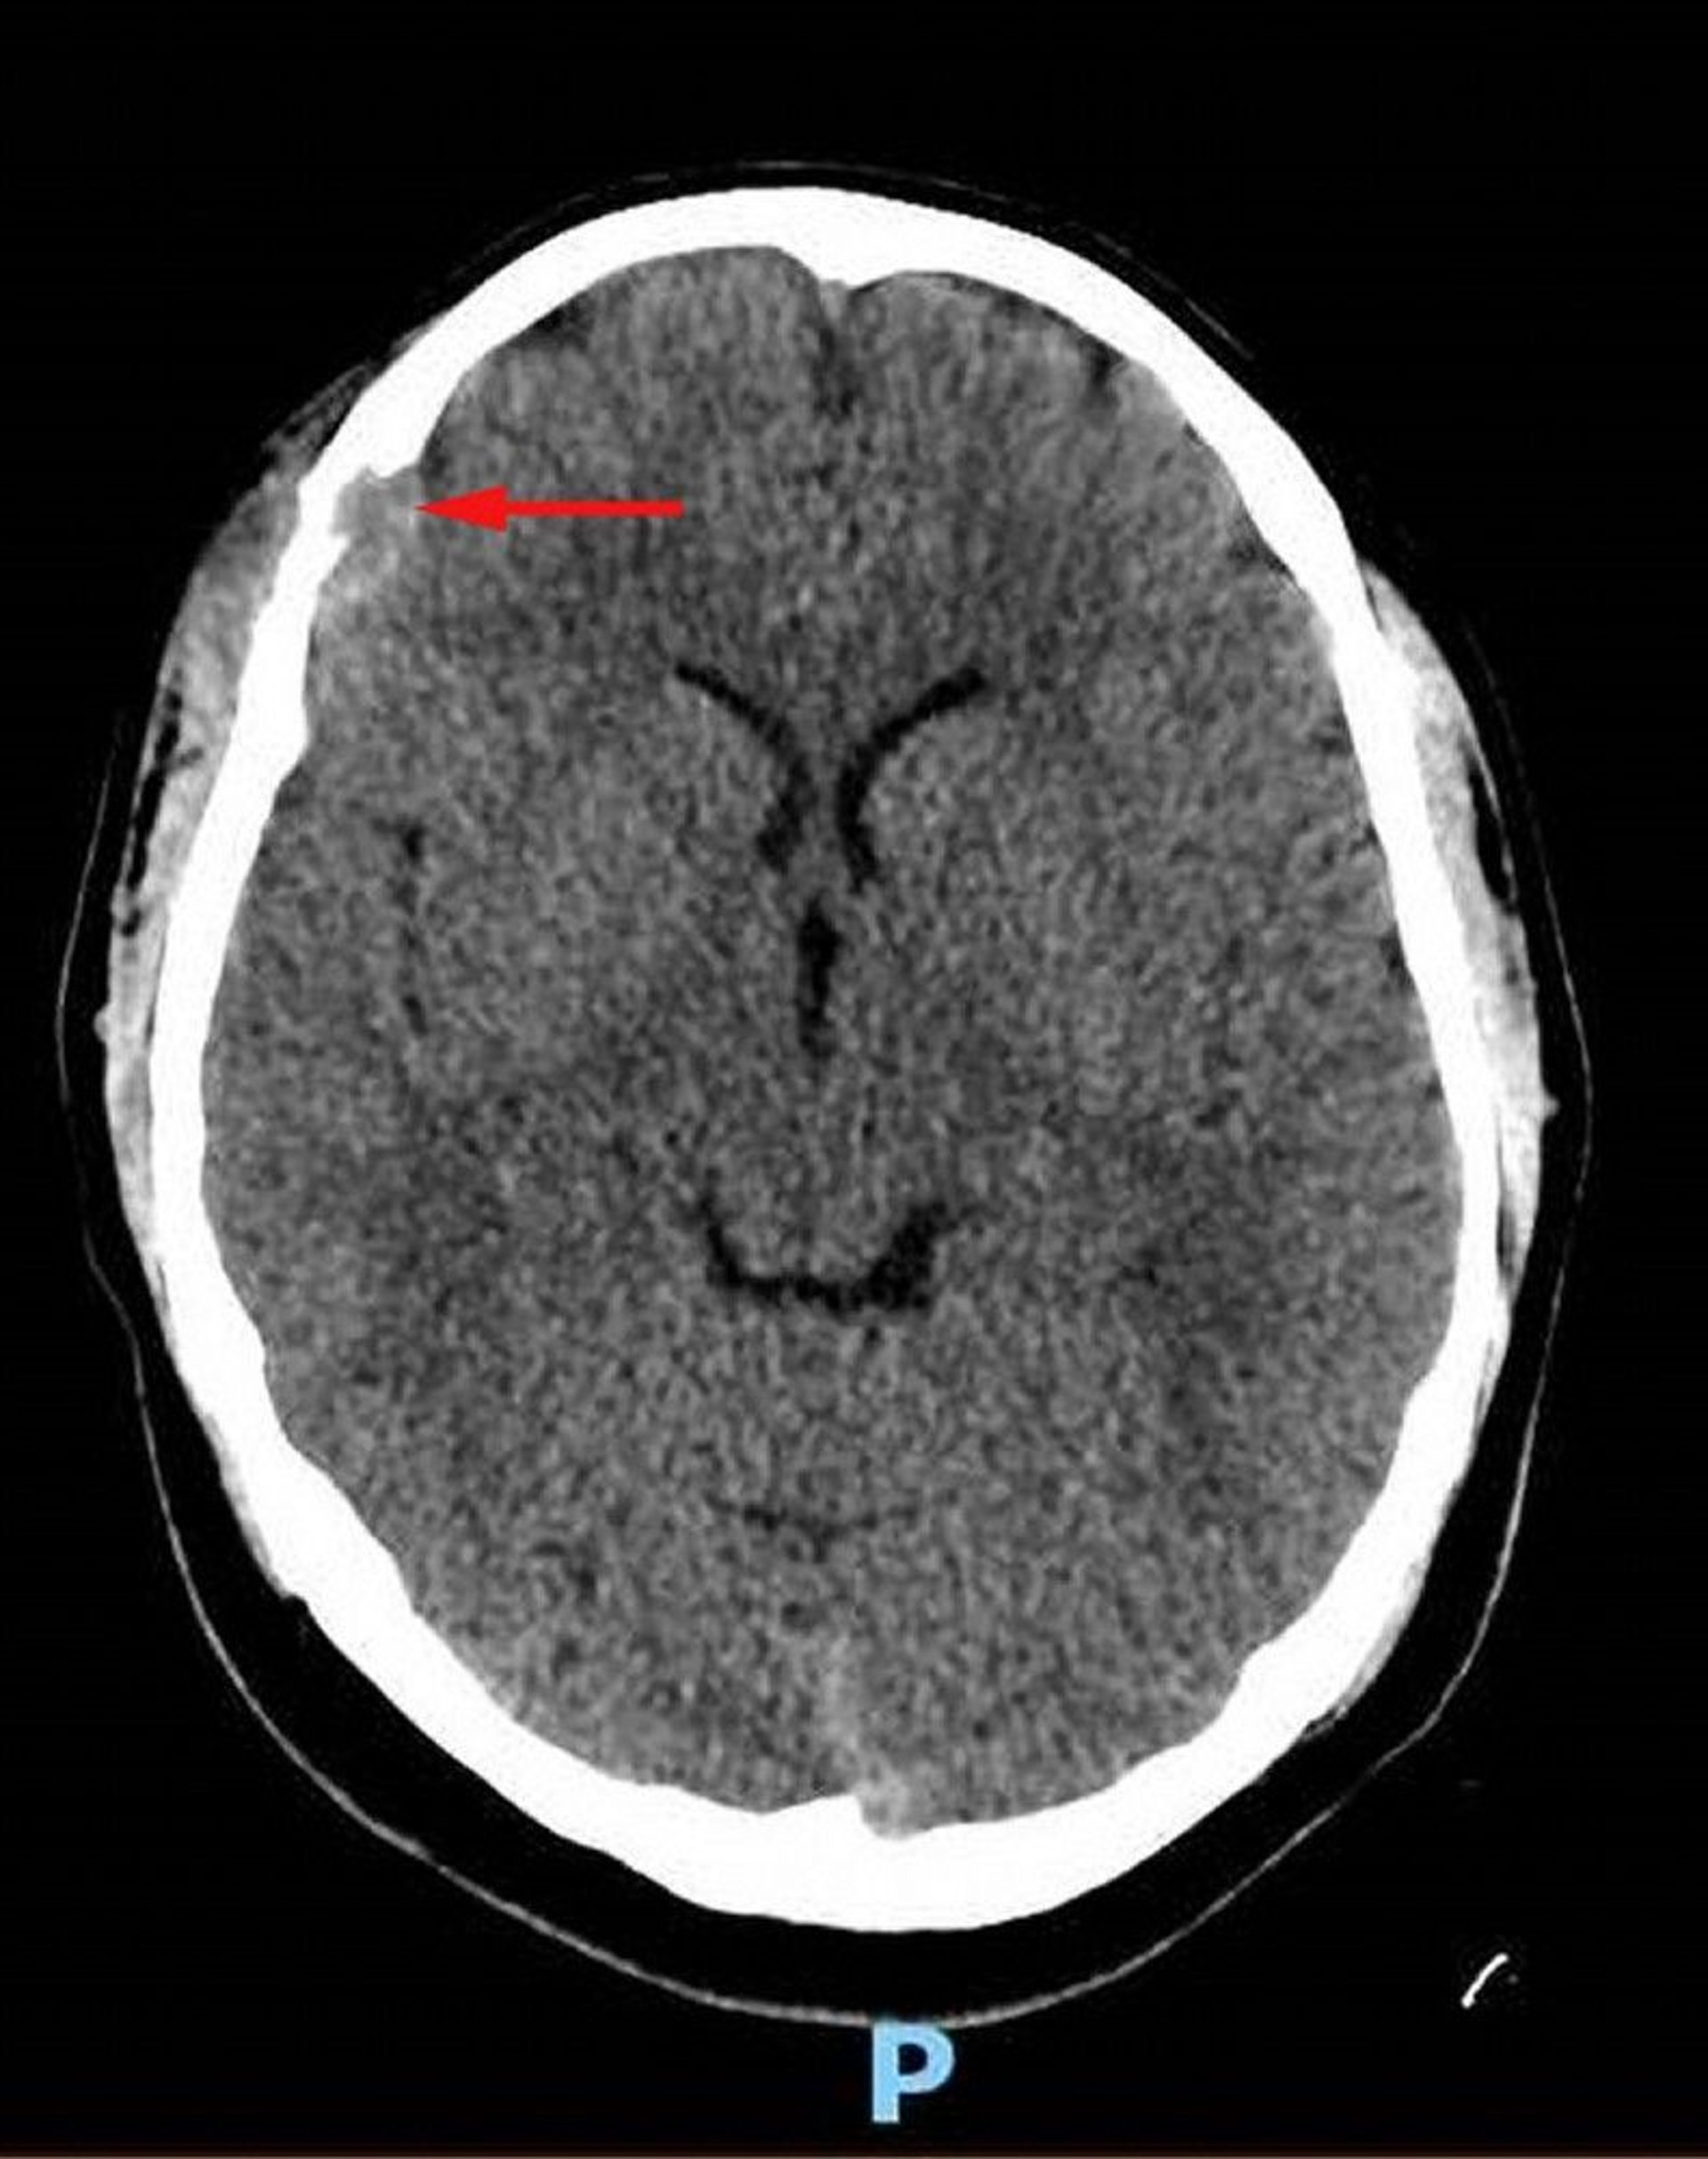

Langerhans Cell Histiocytosis (Head CT)

This image shows a soft-tissue lesion in the right frontal bone with associated osseous destruction and intracranial extension of soft tissue into the dural space (red arrow). Asymmetric overlying scalp soft tissue is present. Biopsy was diagnostic for Langerhans cell histiocytosis.

Image courtesy of Carolyn Fein Levy, MD, and Jeffrey M. Lipton, MD, PhD.